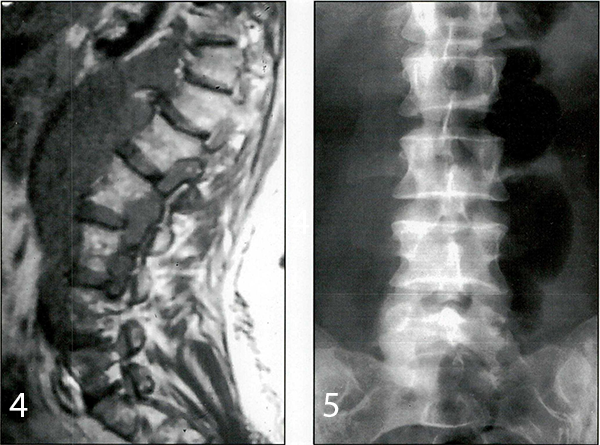

Caso 2: paciente de sexo femenino y 33 años de edad, sin antecedentes significativos, consultó por dolor radicular en el territorio L5 derecho de un año de evolución. Las IRM mostraron sólo signos de degeneración artrósica discal múltiple. La radiografia simple mostró una megapófisis transversa de L5 derecha que se articulaba con el sacro (Fig. 2). Se interpretó que ésta era la causa de sus síntomas y la paciente fue llevada a cirugía para resecar la megapófisis.

Fig. 2. Rx simple que muestra una megapófisis transversa de L5.

Caso 3: paciente de sexo femenino y 23 años de edad, con antecedentes de haber sido operada en su infancia de un tumor neurogénico abdominal, concurrió a la consulta con IRM que mostraban un tejido blando hiperintenso con respecto al LCR entre D12 y L4, ubicado en el espacio pre y paravertebral retroperitoneal, que se introducía dentro del canal espinal a través de los forámenes (Figs. 3 y 4). La paciente estaba asintomática. La oncóloga solicitó una biopsia para conocer la patología y luego poder indicar el tratamiento definitivo.

Fig. 3. IRM axial ponderarla en T1 que muestra un tejido blando hiperintenso con respecto al LCR ubicado a nivel extra e intraforaminal que invade el canal espinal.

Fig .4. IRM sagital pondera d a enT 1 que muestra un tejido blando hiperintenso con respecto al LCR ubicado extensamente a nivel prevertebral e intraforaminal.

Flg. 5. Rx simple postoperatoria que muestra la falta de la megapófisis transversa de L5.

El dolor radicular desapareció en los casos 1 y 2 en el postoperatorio inmediato. La biopsia en el caso 1 fue informada como tejido inespecífico y en el caso 3 como ganglioneuroma. En el caso 2 la radiología postoperatoria confirmó la resección de la megatransversa (Fig. 5). El dolor postoperatorio respondió fácilmente a los analgésicos comunes. En los tres casos el alta se produjo a las 72 horas sin complicaciones.